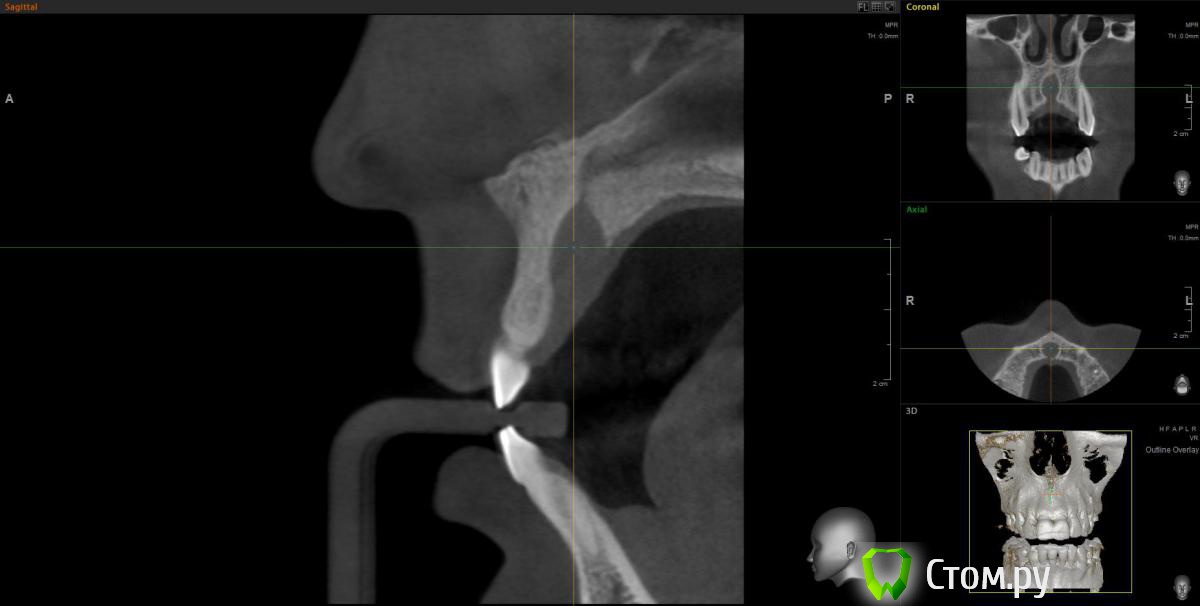

kriokov Опубликовано 20 марта, 2012 Поделиться Опубликовано 20 марта, 2012 Пац 60 лет, 13.03- диагносцирована нагноившаяся киста в\челюсти, вскрыт гнойник, антибактериальная и симптоматическая терапия. На КТ киста до 4 куб см ориентировочно, сквозной дефект с вестибулярной на небную поверхность, деструкция носонебного канала, деструктивный очаг небно за корнем 11. дно носа не критично. Имплантация в перспективе не планируется.Через 1 месяц планируется штатная цистэктомия с удалением 21 и 22. Коллеги, кто как небно мебрану выставляет? Дефект кости на небе 10 на 10 мм. Сам думаю, что под полнослойный лоскут на небе придется устанавливать, попробую отслоиться со стороны костной раны. Ссылка на комментарий

K_gur Опубликовано 3 июня, 2012 Поделиться Опубликовано 3 июня, 2012 Господа ! Пациенту 2009 - ом было 62 года, киста на 11-ом , решили одномоментное удаление, цистэктомия, аугментация и имплантация, Вот снимки! подледный снимок новый. Будут ли замечания? Но самое интересное что пациент да сей пор не добрался до ортопеда, сделает коронку выложу и этот снимок.http://s019.radikal.ru/i625/1206/30/434cde3231d2.jpghttp://s019.radikal.ru/i630/1206/cc/20a47ecf2a78.jpg http://s06.radikal.ru/i179/1206/49/7f6119696343.jpghttp://s019.radikal.ru/i604/1206/d6/77c4408b76ff.jpg http://i064.radikal.ru/1206/74/5f59a960ba3d.jpghttp://s017.radikal.ru/i440/1206/ad/40fae14fa38a.jpg Ссылка на комментарий

wladdX Опубликовано 22 января, 2014 Поделиться Опубликовано 22 января, 2014 (изменено) Пациентка 33-х лет, обратилась с жалобами на болезненную припухлость на тв. нёбе. При обследовании выявлена киста резцового канала, самопроизвольно вскрывшаяся.Через перф.отверстие отмыта, воспаление стихло, свищевого хода не сформировалось (перф.отверстие эпителизировалось). Встаёт вопрос об операции. Планируется нёбный доступ. Как думаете, коллеги? Изменено 22 января, 2014 пользователем wladdX Ссылка на комментарий